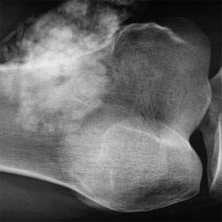

(Справа) Рентгенография в ЗП проекции: определяется типичная картина трубчатых костей кисти при талассемии, при которой наблюдается преобладание гиперплазии костного мозга. Все кости приобретают квадратную форму или теряют нормальную форму, что обусловлено накоплением костного мозга. (Слева) Рентгенография бедренной кости ребенка в ПЗ проекции: определяется нарушение формирования нормальной полости в дистальном метафизе. Это напоминает картину по типу колбы Эрленмейера при болезни Гоше, являющейся болезнью накопления. В этом случае костный мозг упакован в кроветворные ячейки.